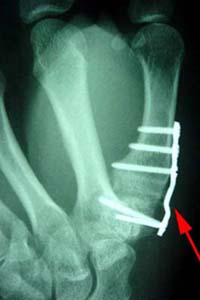

A joint fusion using a plate and screws at the base of the thumb.